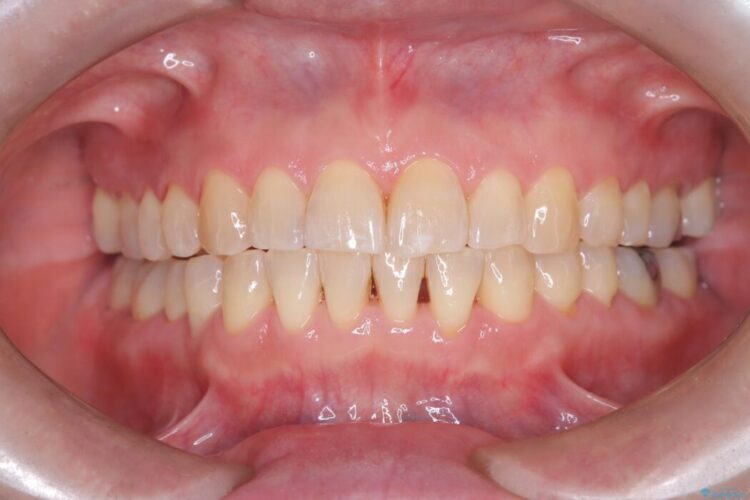

ワイヤー矯正ならではの確実な歯のコントロールにより、当初の計画通り約1年という短い期間で、前歯のガタつきが解消。見た目が美しく整っただけでなく、清掃しやすい機能的な歯並びを獲得していただけました。